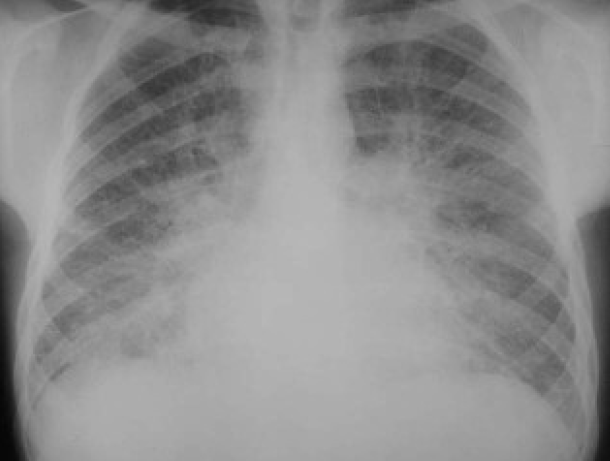

Left middle lobe pneumonia versus normal lung

Comparison of a normal lung and left middle lobe pneumonia